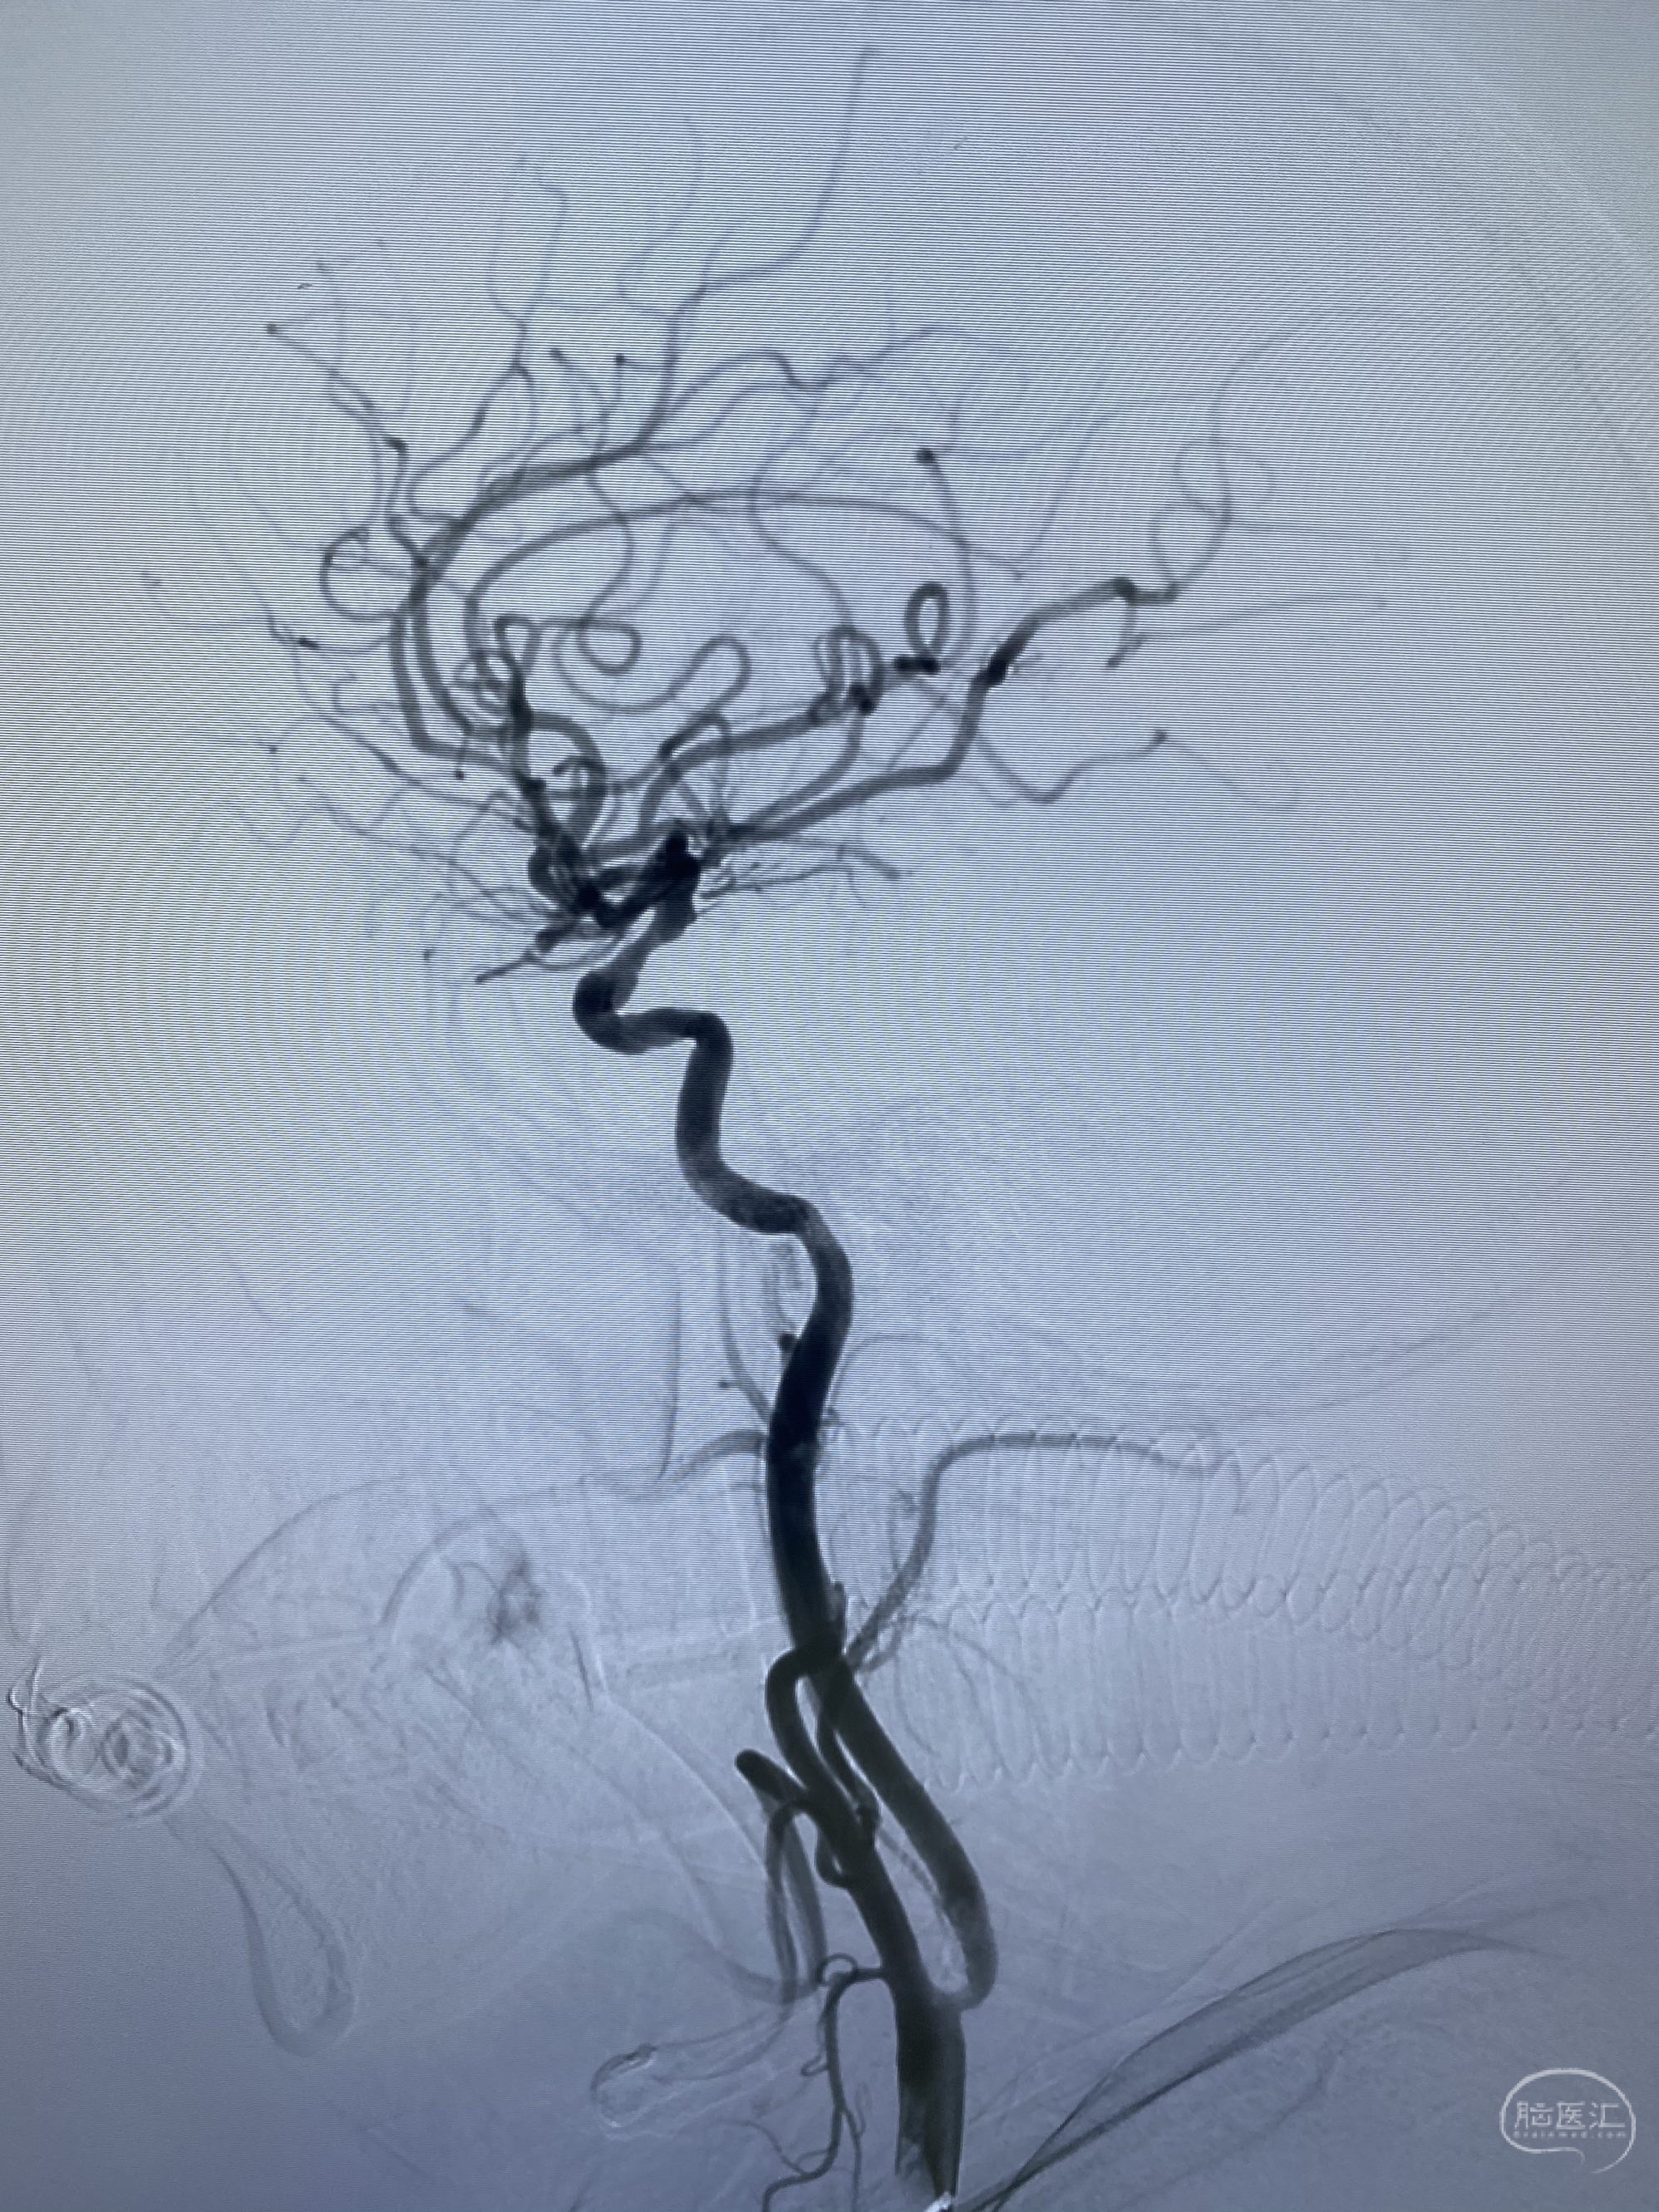

今日手术,TJG,M62Y,一期左侧颈动脉狭窄支架植入,二期椎动脉V4段多发夹层动脉瘤伴狭窄,常规支架辅助栓塞方法复杂又危险,血流导向装置植入快捷又安全。南阳市中心医院神经内科脑血管病介入团队pipeline flexFD植入两人导师资格。

椎动脉颅内段多发夹层动脉瘤伴载瘤动脉狭窄pipeline flex植入

今日手术,TJG,M62Y,一期左侧颈动脉狭窄支架植入,二期椎动脉V4段多发夹层动脉瘤伴狭窄,常规支架辅助栓塞方法复杂又危险,血流导向装置植入快捷又安全。南阳市中心医院神经内科脑血管病介入团队pipeline flexFD植入两人导师资格。